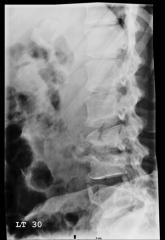

A 54-year-old man presents with a complaint of a two-week history of severe low back pain. He denies any injury or trauma. The pain is so severe that ...